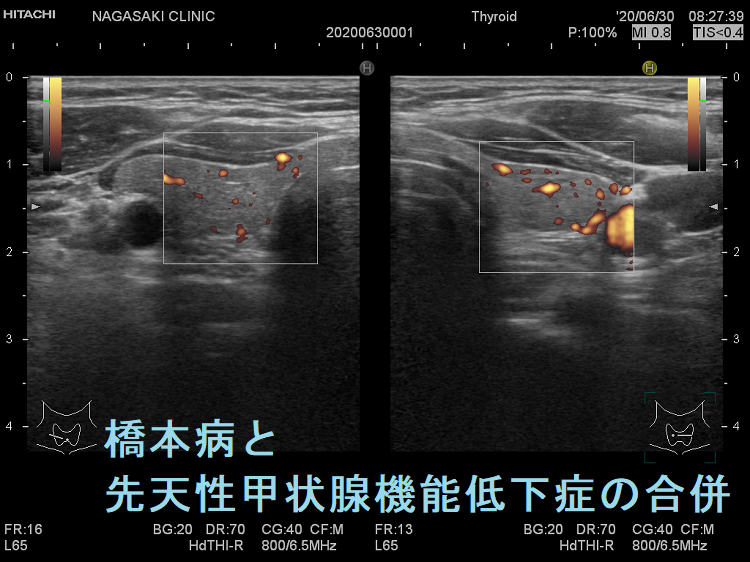

遺伝性甲状腺ホルモン合成障害に橋本病(慢性甲状腺炎)を合併

遺伝性甲状腺ホルモン合成障害に、橋本病(慢性甲状腺炎)を合併する事があります(橋本病も約70%は遺伝性です)。

あくまで仮説ですが、甲状腺ホルモン合成障害で血中サイログロブリンが上昇すると、それに対する抗サイログロブリン抗体産生が誘発され、橋本病が発症する可能性が考えられます。(第55回 日本甲状腺学会 P2-01-10 TSH 遅発上昇により新生児マススクリーニングをすり抜けた複合ヘテロ接合性DUOX2 異常症に橋本病を合併した女児例)

橋本病(慢性甲状腺炎)に遺伝性甲状腺ホルモン合成障害の軽症例を合併

橋本病(慢性甲状腺炎)を合併すると、遺伝性甲状腺ホルモン合成障害の軽症例がマスクされ、あたかも甲状腺機能正常橋本病による腺腫様甲状腺腫のように見えます(橋本病も約70%遺伝です)。